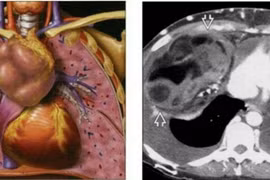

Đau vai gáy 6 năm nhưng chị Vũ Thị Th. (55 tuổi, ở Hưng Yên), nghĩ là do mình làm nghề thợ may, phải ngồi nhiều. Tuy nhiên, khi cơn đau tăng nặng và đi khám, bác sĩ chẩn đoán bệnh nhân bị u trung thất trước kích thước lớn xâm lấn tim và phổi.

(khoahocdoisong.vn) - Nhờ sự kết hợp nhiều chuyên khoa các bác sĩ Bệnh viện Bạch Mai đã cứu bệnh nhân có khối u trung thất lớn xâm lấn tim, phổi, làm tắc mạch...